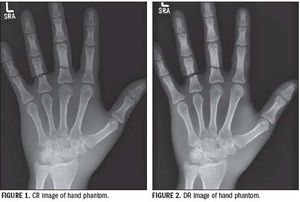

Digital radiography is now the standard technology for X-ray imaging. Computed radiography and solid-state (flat-panel) digital radiography are digital X-rays main detector systems.